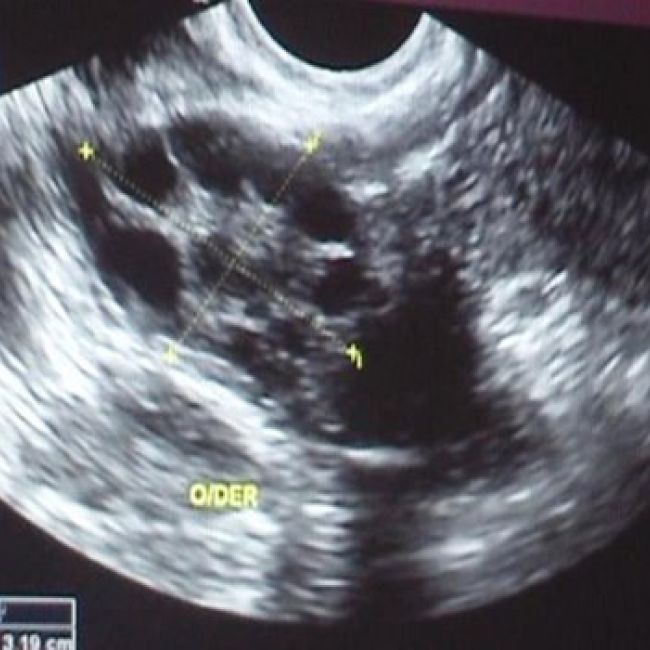

• Ecografías

• Ecografía 3-4-5D

• Ecografía 20 semanas o morfológica en 5D